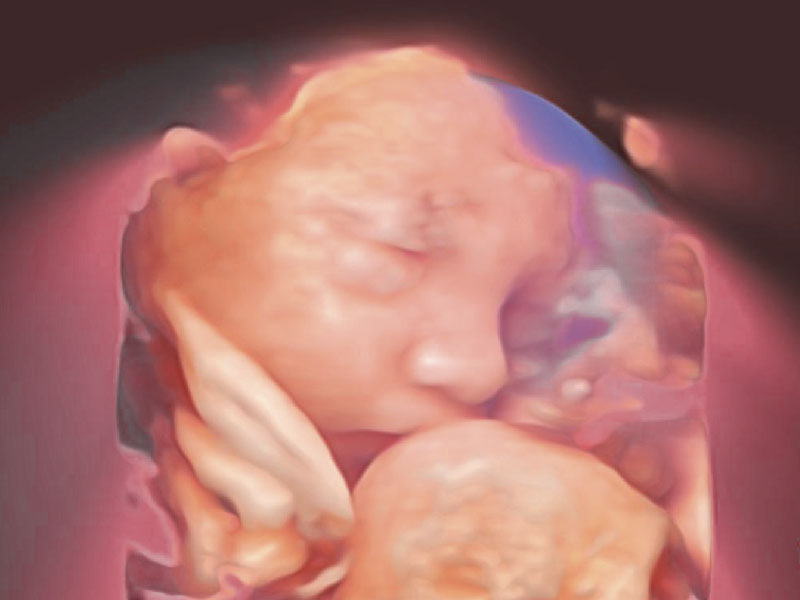

Auto Face

Tự động nhận diện khuôn mặt

Tự động tối ưu hóa khuôn mặt thai nhi 3D

Tự động loại bỏ tình trạng tắc nghẽn ở phía trước khuôn mặt thai nhi

Nhận dạng chính xác cấu trúc giải phẫu khuôn mặt thai nhi